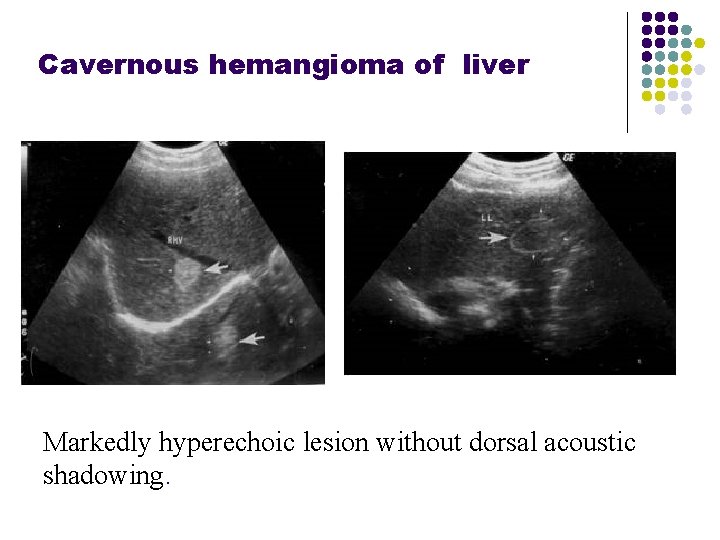

Cavernous hemangioma of liver Markedly hyperechoic lesion without dorsal acoustic shadowing.